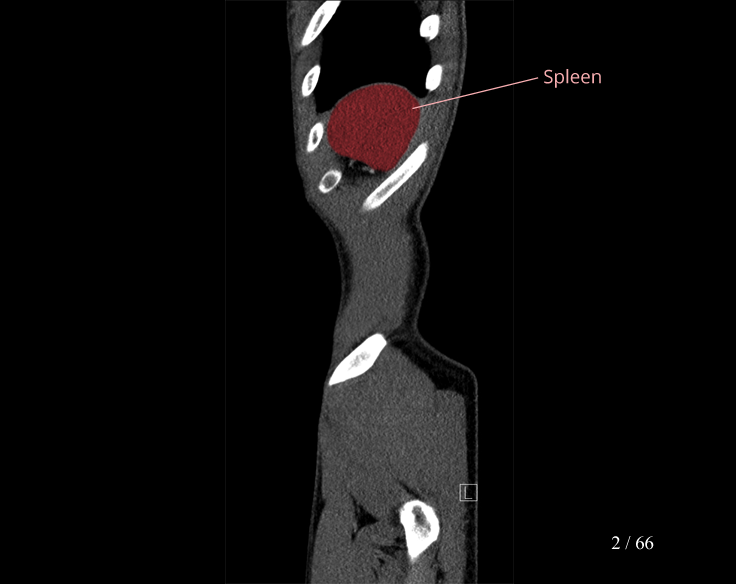

Body

Covers abdominal CT anatomy.